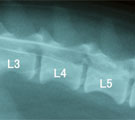

初診時。両後肢の対麻痺で起立不能。 脊髄造影。L4-L6にかけ背腹両方に造影剤の充填欠損がみられ脊髄全体の腫脹が示唆された。 術後2日で自ら起立して食事を食べれるようになった。

経過:受診時、後肢不全麻痺にて起立不能だった。痛覚認知はあった。同日、脊髄造影にてL4-L6に脊髄自体が腫大して生じたような造影剤充填欠損像が認められた。翌日、L4-L6において片側椎弓切除術による脊髄の減圧術を行った。術中、硬膜に接して砂状塊状物あり、後に病理検査で「砂粒腫型髄膜腫」と診断された。術後2日で自分で立って食事を食べれるようになった。7日後には10m位歩けるようになり経過良好であった。